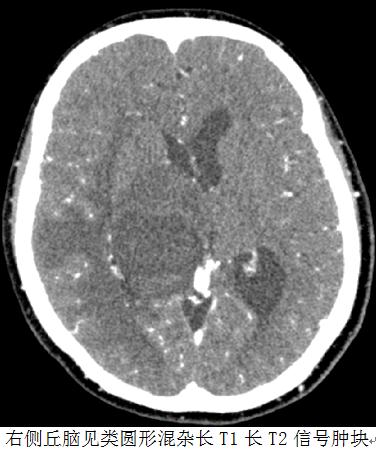

患者于2016年7月无明显诱因出现头晕不适,伴双下肢乏力、食欲不振,无明显头痛、头胀,无恶心、呕吐等不适,就诊于当地医院,行颅脑CT检查,提示颅脑占位。后患者转诊于山东省立医院,于2016-07-13行颅脑强化MRI检查,提示右侧丘脑见类圆形混杂长T1长T2信号肿块,大小约3.4X3.3X2.8cm,内部信号欠均匀,弥散受限,增强扫描肿块明显环状强化,局部呈结节样改编。影像学诊断:符合右侧丘脑恶性肿瘤MR表现,考虑胶质母细胞瘤可能大。后患者曾就诊于天坛医院,建议手术。患者家属考虑手术创伤较大,不同意手术治疗。

右侧基底节区可见一囊状低密度肿物,可见囊壁环状及小结节样强化,囊灶最大截面约4.1cmx3.0cm,其上方实质内见散在金属粒子显示,肿块周围大片不规则低密度区,右侧脑室及中脑导水管受压、变形,中线结构向左侧移位,脑室系统部分增宽;与(2017-3-10CT)对照肿块囊性部分及水肿范围较前略增大。